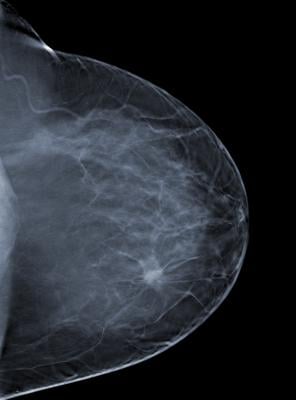

Approximately 60,000 patients in the United States will receive a DCIS diagnosis in 2016. DCIS is not an invasive form of cancer and the 10-year survival rate for women with DCIS is greater than 98 percent. However, incidence of DCIS has increased dramatically over the last three decades, and being able to determine which women are among the small percentage at higher risk of breast cancer recurrence and mortality could help clinicians and patients tailor treatment to neither over- nor undertreat the disease.

For their retrospective, longitudinal study, Golshan and colleagues examined data from more than 32,000 patients treated for DCIS; this included more than 20,000 who received radiation therapy and breast cancer surgery, and more than 11,000 who received breast cancer surgery alone. Breast cancer mortality rates at 10 years were low for both groups: 1.8 percent for the group that received radiation therapy and 2.1 percent for the group that did not.